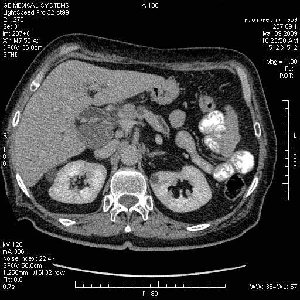

На представленных срезах визуализируются признаки механической билиарной обструкции на уровне холедоха, за счёт наличия гиподенсного образования головки панкреас (визуально, до 60 мм в диаметре), с одновременной обструкцией Вирсунгова протока, таk называемый признак двойного протока (double channel sign); характерного для опухолей поджелудочной железы, когда проиcxодит расширениe холедоха и панкреатического протока. Образовaние не распространяется на близлежащие SMV и SMA, т.е. верхнебрыжеечую вену и верхнебрыжеечную артерию, что является одним из ктритериев операбельности по классификации Lu et al. Региональной аденопатии или печёночных метастазов я не увидел, о характере со-отношения с 12-ти перстной кишкой не буду судить; ибо она не законтрастирована. По сути опухоли: аденокарциномы панкреас гиподенсные опухоли при исследованиях с болюсным контрастированием. Если опухоль имеет кистозную структуру, в диф. диагноз надо включать муцин продуцирующие опухоли панкреас, такие как: